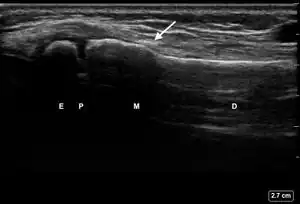

| 1 | No Fracture | "Unbroken" |

![]() Ultrasound lateral view of normal radius. E = epiphysis; P = physis; M = metaphysis; D = diaphysis. | |